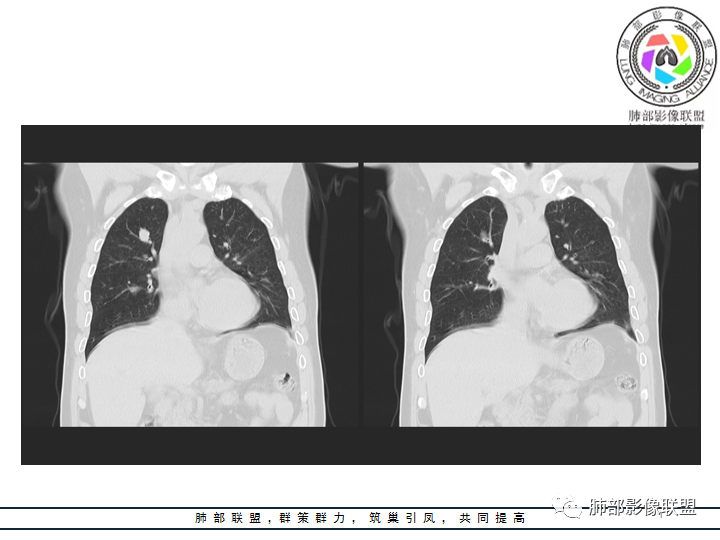

影像资料

老年男性患者,长期吸烟史,没有呼吸系统临床表现。胸部CT示右肺上叶实性密度结节影,密度均匀,未见空洞及钙化,边缘较光整,未见分叶及毛刺。血管影旁现侧出,支气管进入并截断,不均匀强化。

影像上结节影或块影一旦与支气管密切相关(如截断),不支持硬化性肺细胞瘤、错构瘤、孤立性纤维瘤等良性病灶。如此清晰的边缘也不符合一般意义上的炎性渗出。